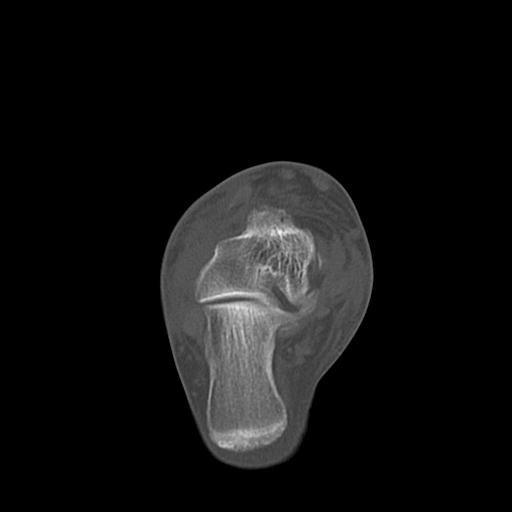

49554 3/13 膝 4R 3/16 4R 1/18 2R 78歳男性 膝蓋骨骨折